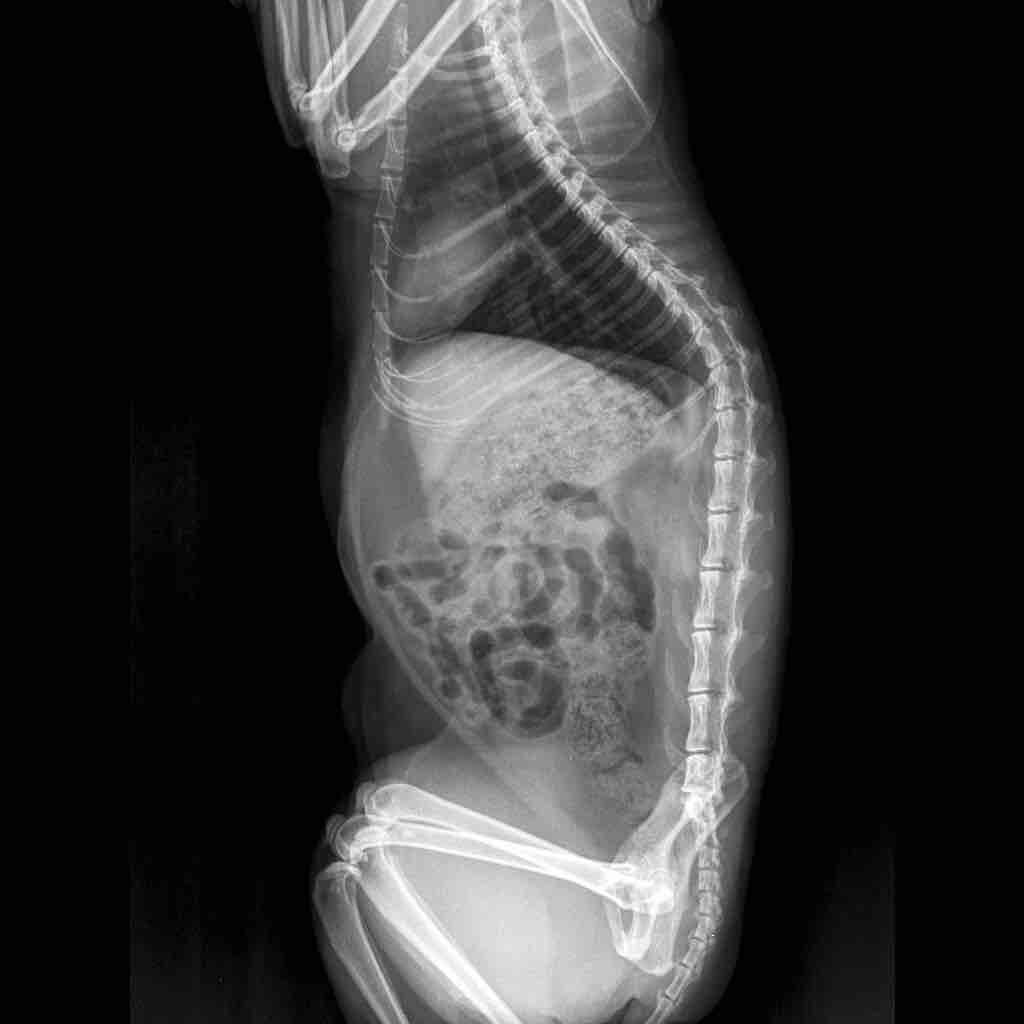

I got an abdominal x ray of my cat today. Looking at it, my vet said that her bladder is full of stones. But after comparing the x Ray to those online, I don’t see them. Could you please take a look at these x rays and tell me if there are crystals or stones present? Thank you very much

The back legs are tucked up over the bladder, so it is hard to say for certain, but I do not see any large stones in the urinary bladder. I would need to spin down a sample of urine and look at it under a microscope to see if there are urinary crystals since those do not show up on x-rays.